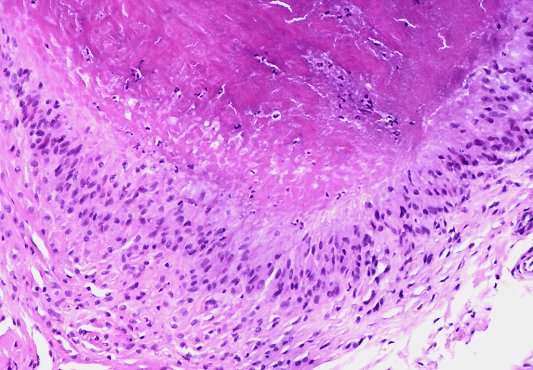

Кольцевидная гранулема – это хроническое доброкачественное заболевание кожи, клинически проявляющееся кольцевидно расположенными папулами (узелками), а патоморфологически – гранулематозным воспалением.

Клинические проявления. Мелкие плотные узелки, слегка возвышающиеся над уровнем кожи группируются в кольца или полукольца разной величины, чаще в виде множественных фигур. Центральная часть колец несколько западает. Элементы имеют цвет нормальной кожи, иногда с бледно-розовым, серовато-красным оттенком.

Преимущественная локализация — тыльная поверхность кистей и стоп, часто около суставов. У детей нередко наблюдается атипичная локализация — на лице, туловище, ягодицах. Очаги поражения могут быть как единичными, так и множественными. В некоторых случаях кожный процесс может носить распространенный и генерализованный характер. Кольцевидная гранулема обычно не имеет чешуек (шелушения) на поверхности и субъективно не беспокоит.

Кольцевидная гранулема может проявляться в виде подкожных очагов (чаще встречается у детей), представляющих собой плотные узлы, безболезненные при пальпации. Типичная локализация — передняя поверхность голеней, пальцы кистей и волосистая часть головы. Кожа над узлами не изменена.

Диагностика. Диагноз кольцевидной гранулемы обычно устанавливается на основании данных клинической картины, но может быть подтвержден при биопсии кожи.